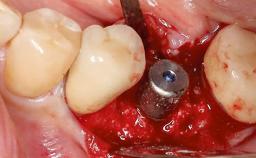

Surgical Management of Peri-Implantitis: Open-Flap Debridement with Seven-Year Follow-up After Treatment

This case describes both a surgical and an anti-infective approach for the management of peri-implantitis, including treatment of the entire dentition to eliminate any deep periodontal pockets that could serve as reservoirs for bacterial re-colonization at the implant site. A 65-year-old female patient was referred to the periodontist in 2013 for assessment and management of an infection at implant 12. On examination, probing depths at implant 12 were 11 mm with suppuration and bleeding on probing.